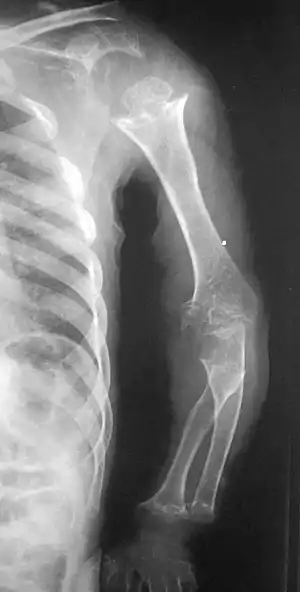

| Pseudoachondroplasia. Shoulders and Humeri. Note the dysplastic proximal humeral epiphyses, metaphyseal broadening, irregularity and metaphyseal line of ossification. These changes are collectively known as "rachitic-like changes". Lesions are bilateral and symmetrical. | |

- Dysplastic/hypoplastic epiphyses especially of shoulders and around the knees.

- Metaphyseal broadening, irregularity and metaphyseal line of ossification. These abnormalities that are typically encountered in proximal humerus and around the knees are collectively known as “rachitic-like changes”.

- Radiographic lesions of the appendicular skeleton are typically bilateral and symmetric.